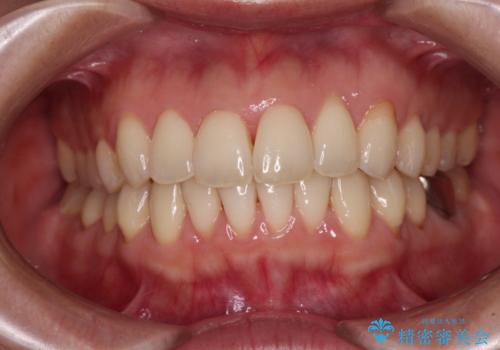

- 上下の前歯のデコボコを気にして来院された患者様です。

妊娠中であり、途中通院が難しくなる可能性があることから、インビザラインによる矯正治療を行うこととしました。

上下顎歯列全体の後方移動とIPR(歯と歯の間を削る)によってデコボコが解消するように設計しました。